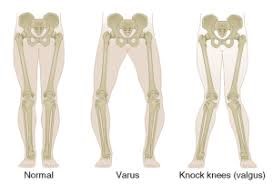

La rodilla es la articulación formado entre tres huesos el fémur, la patela y la tibia. A diferencia de la cadera, la rodilla tiene tres compartimientos funcionales muy definidos: la femorotibial medial (la parte de dentro de la rodilla), la femorotibial lateral (la parte de fuera de la rodilla) y la femoropatelar (la parte anterior de la rodilla). Es una articulación sometido a carga y predispuesto a sufrir desgaste. La artrosis tiene un componente genético y familiar muy importante en su aparición y también en la deformidad presentada por el paciente. La deformidad de piernas más frecuente es la deformidad con las piernas arqueadas hacia dentro (genu varo) en casi 90% de casos. Algunas veces la piernas se deforman hacia fuera (genu valgo). Según la deformidad con la que presenta la rodilla puede afectar un compartimiento, dos o todos cuando la enfermedad es avanzada.